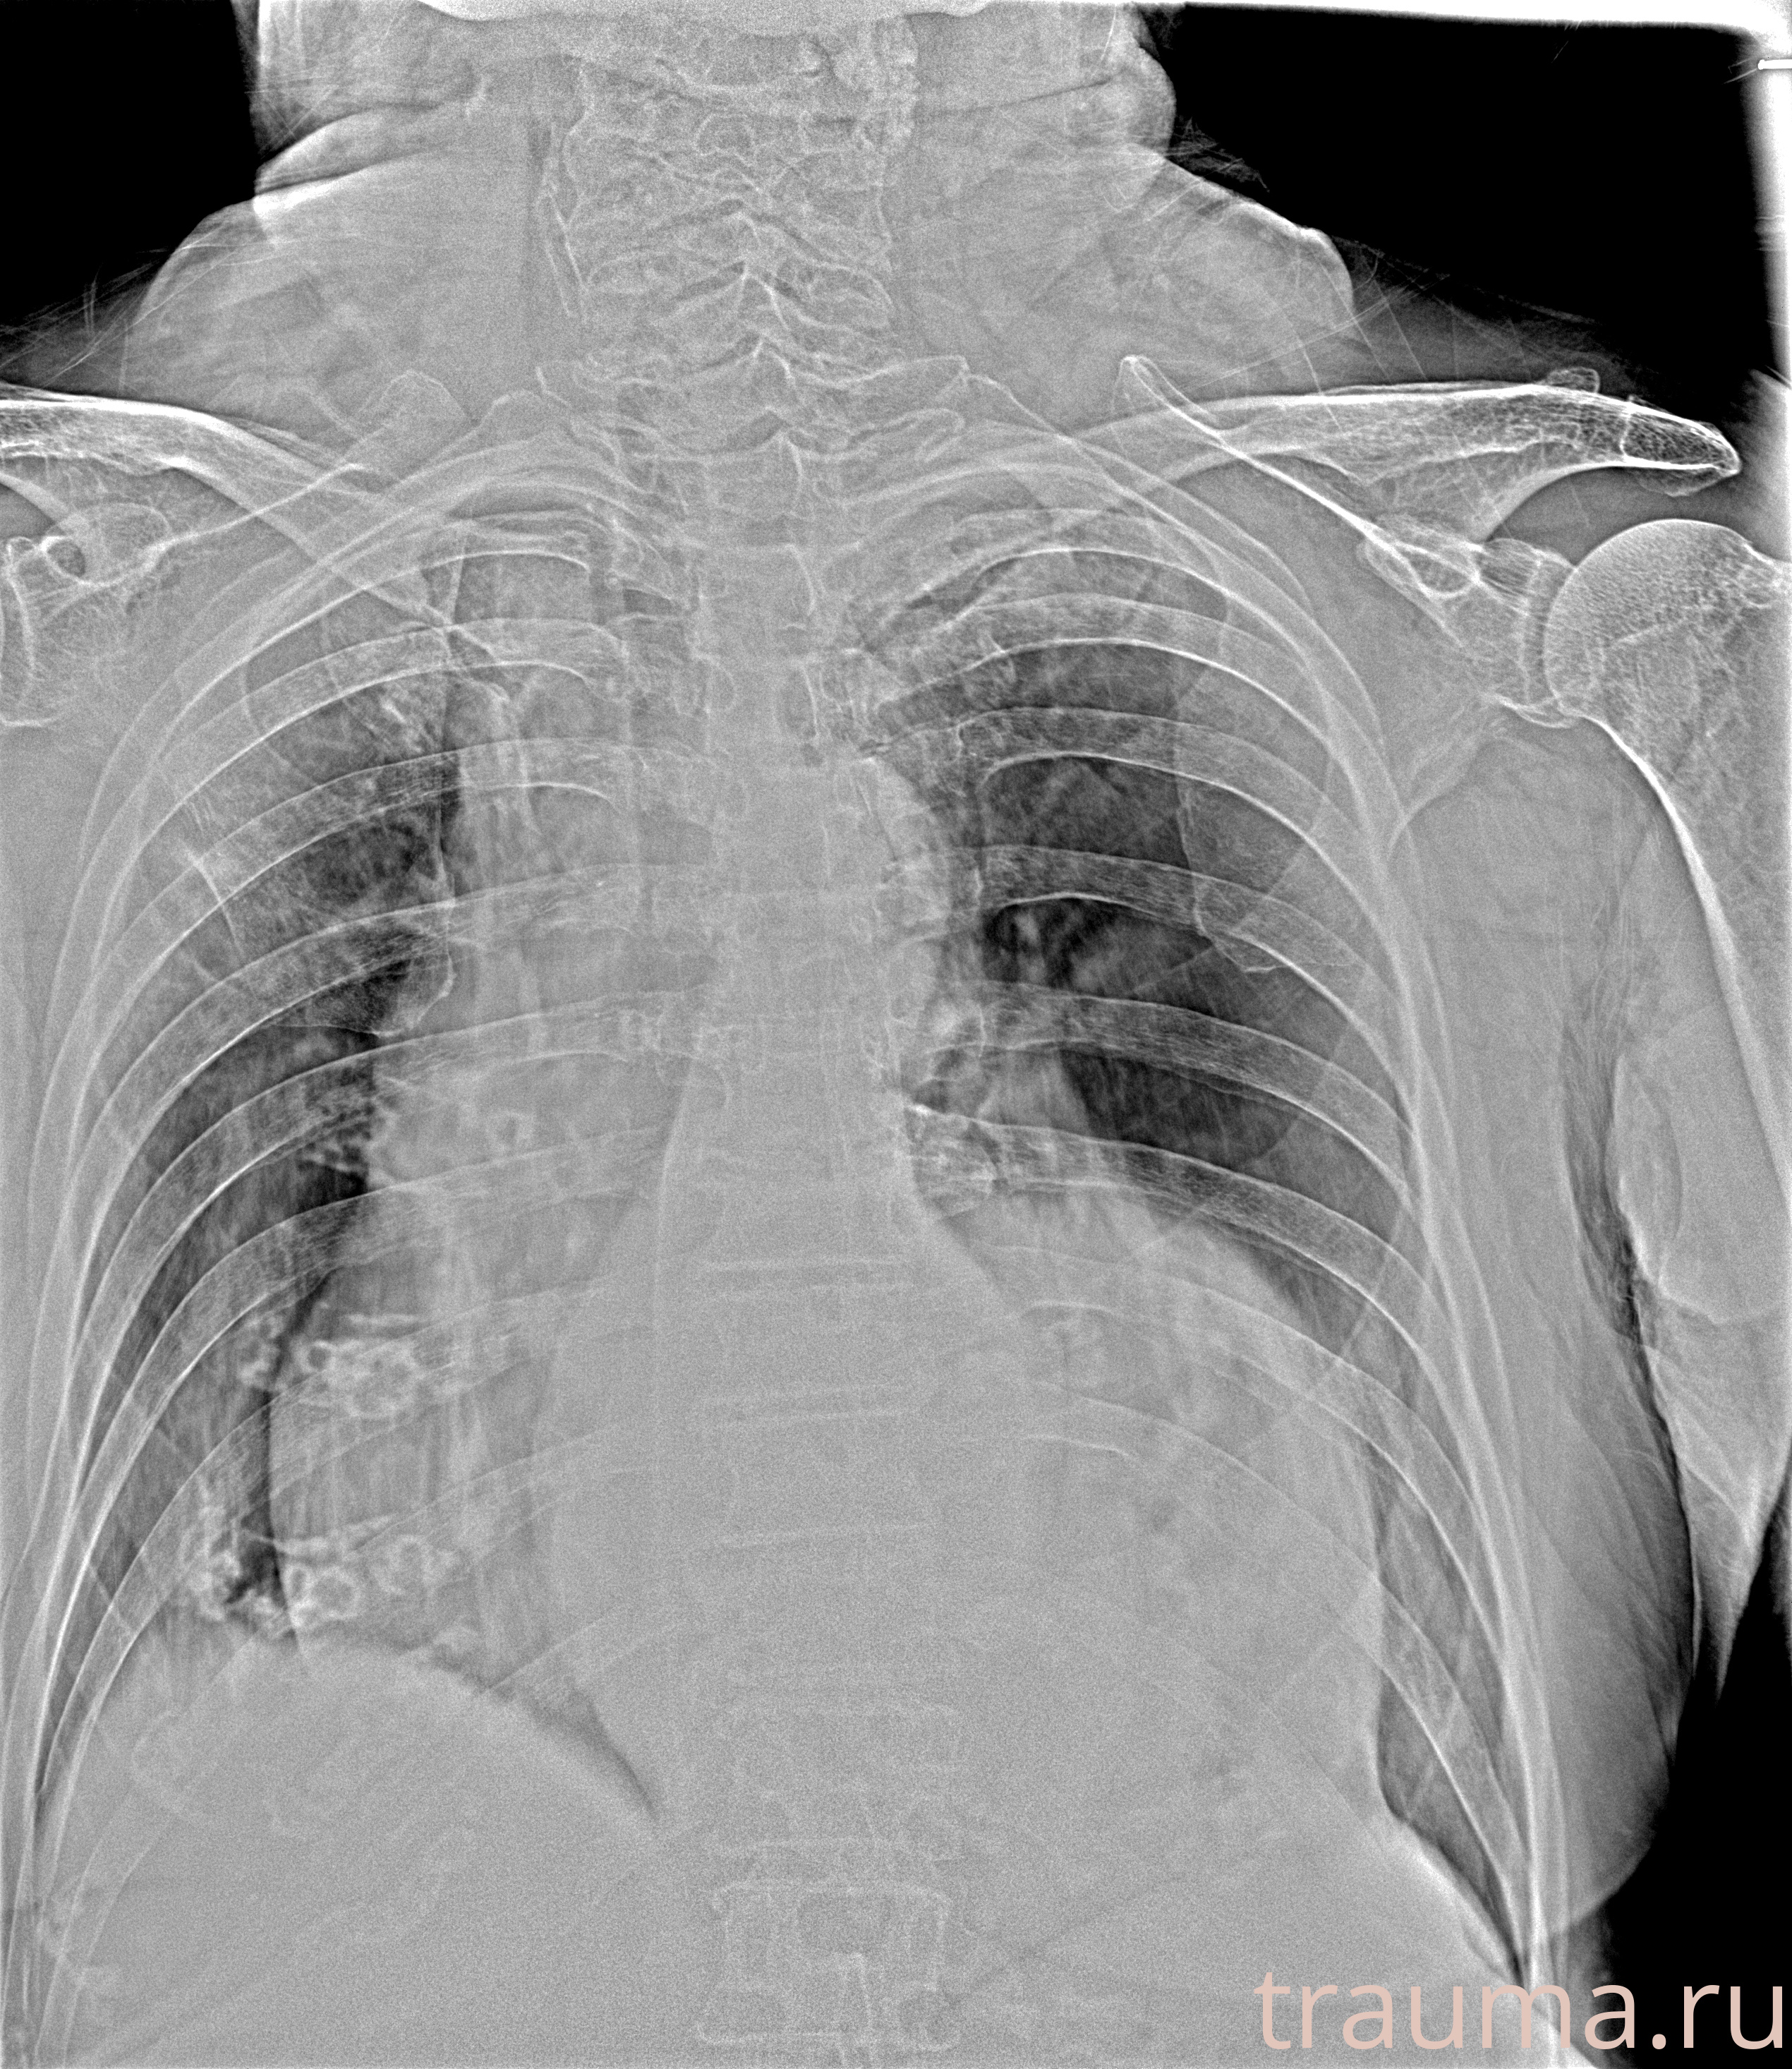

Рентген на дому: по вашему адресу приезжает врач-рентгенолог, травматолог-ортопед с мобильным рентгеновским аппаратом, проводит диагностику травмы или заболевания, делает необходимые рентгенограммы, дает рекомендации по дальнейшему лечению. Получить качественные снимки в домашних условиях возможно благодаря уникальной методике, разработанной МосРентген Центром для института  Склифосовского

при переломе шейки бедра и пневмонии от компании МосРентген Центр - партнера Института имени Склифосовского